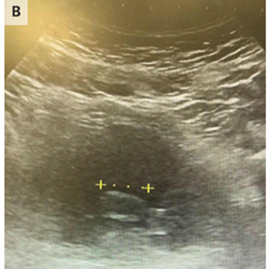

超音波検査により、膀胱床に2㎝の可動性の塊があることが分かった。